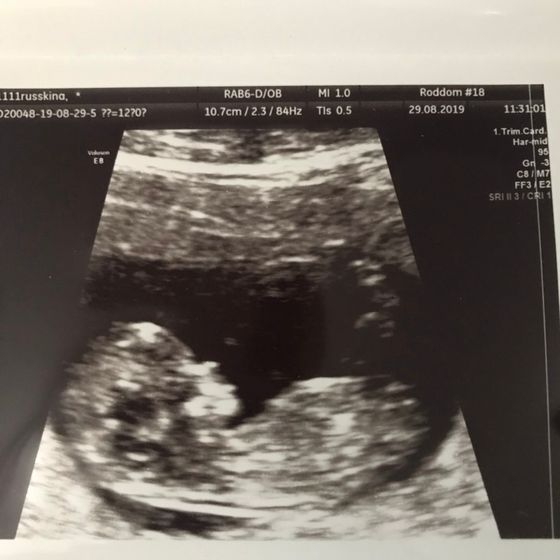

Сходила вчера на 1 скрининг, сказали все замечательно, пол не предположили, рано.

Но вот хорион меня смущает… Узист ничего не сказала. Это опасно?

И ещё по КТР какие-то непонятки. По таблицам КТР на 12.2 недели, а поставили 11.5?